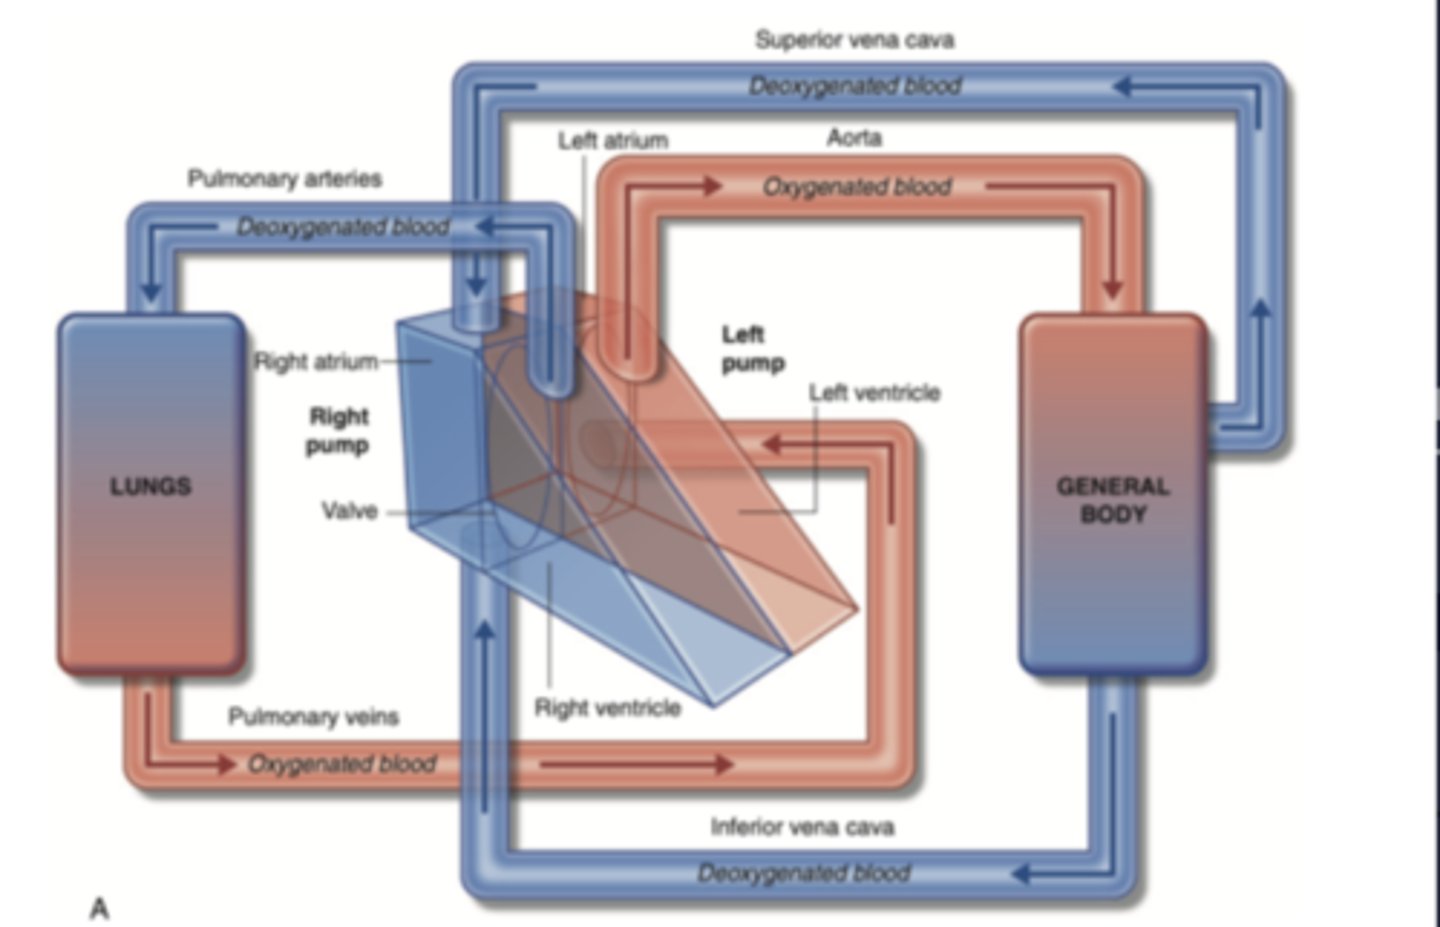

SYSTEMIC CIRCULATION

flow of blood from body tissue to the heart and then from the heart back to body tissues

It carries oxygen and nutrients to the cells and picks up carbon dioxide and waste products

Describe in detail systemic circulation

From the left ventricle, oxygenated blood,

through the arteries,

to the capillaries in the tissues of the body.

From the tissue capillaries, the deoxygenated blood

returns through a system of veins to the right atrium of the heart. (superior and inferior cava veins)

PULMONARY CIRCULATION

Circulation of blood between the heart and the lungs

transports oxygen-poor blood from the right ventricle to the lungs,

where blood picks up a new oxygenated blood

Describe in detail pulmonary circulation

From the right ventricle poor oxygenated blood is impulsed

to the lungs, through the pulmonary artery

blood is oxygenated

returns to the left atria through the pulmonary veins

from where is the right atrium receiving the blood?

From the whole body

Right ventricle pumps blood to?

pulmonary artery

from where receives blood the left atrium?

pulmonary veins

Where pumps blood the left ventricle?

into the aorta